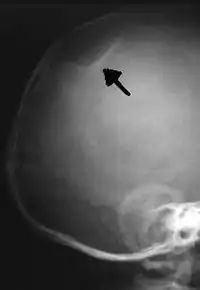

The material factual allegations of the amended complaint are as follows. Plaintiff was born on May 14, 1970. On repeated occasions during the first year of her life she was severely beaten by her mother and the latter's common law husband, one Reyes. On April 26, 1971, when the plaintiff was eleven months old, her mother took her to the San Jose Hospital for examination, diagnosis, and treatment. The attending physician was defendant Dr. Flood, acting on his own behalf and as agent of the defendant San Jose Hospital. At the time, the plaintiff was suffering from a comminuted spiral fracture of the right tibia and fibula, which gave the appearance of having been caused by a twisting force. Plaintiff's mother had no explanation for this injury. Plaintiff had bruises over her entire body. In addition, she had a non-depressed linear skull fracture which was then in the process of healing. Plaintiff demonstrated fear and apprehension when approached. Inasmuch as all plaintiff's injuries gave the appearance of having been intentionally inflicted by other persons, she exhibited the medical condition known as the battered child syndrome.

It is alleged that proper diagnosis of plaintiff's condition would have included taking X-rays of her entire skeletal structure, and that such procedure would have revealed the fracture of her skull. Defendants negligently failed to take such X-rays, and thereby negligently failed to diagnose her true condition. It is further alleged that proper medical treatment of plaintiff's battered child syndrome would have included reporting her injuries to local law enforcement authorities or juvenile probation department. Such a report would have resulted in an investigation by the concerned agencies, followed by a placement of plaintiff in protective custody until her safety was assured. Defendants negligently failed to make such report.

On this appeal plaintiff has expressly abandoned her claim of punitive damages. It is alleged that proper diagnosis of plaintiff's condition would have included taking X-rays of her entire skeletal structure, and that such procedure would have revealed the fracture of her skull. Defendants negligently failed to take such X-rays, and thereby negligently failed to diagnose her true condition. It is further alleged that proper medical treatment of plaintiff's battered child syndrome would have included reporting her injuries to local law enforcement authorities or juvenile probation department. Such a report would have resulted in an investigation by the concerned agencies, followed by a placement of plaintiff in protective custody until her safety was assured. Defendants negligently failed to make such report. The complaint avers that as a proximate result of the foregoing negligence plaintiff was released from the San Jose Hospital without proper diagnosis and treatment of her battered child syndrome, and was returned to the custody of her mother and Reyes who resumed physically abusing her until she sustained traumatic blows to her right eye and back, puncture wounds over her left lower leg and across her back, severe bites on her face, and second and third degree burns on her left hand.

While helpful, the foregoing general history of the battered child syndrome is not conclusive on the precise question in the case at bar. The question is whether a reasonably prudent physician examining this plaintiff in 1971 would have been led to suspect she was a victim of the battered child syndrome from the particular injuries and circumstances presented to him, would have confirmed that diagnosis by ordering X-rays of her entire skeleton, and would have promptly reported his findings to appropriate authorities to prevent a recurrence of the injuries. There are numerous recommendations to follow each of these diagnostic and treatment procedures in the medical literature cited above.

For example, the leading article by Kempe et al., op. cit., supra,[10] states that "A physician needs to have a high initial level of suspicion of the diagnosis of the battered-child syndrome in instances of subdural hematoma, multiple unexplained fractures at different stages of healing, failure to thrive, when soft tissue swelling or skin bruising are present, or in any other situation where the degree and type of injury is at variance with the history given regarding its occurrence . . . ." (Id., at p. 20.) Of the different types of fractures exhibited, an arm or leg fracture caused by a twisting force is particularly significant because "The extremities are the 'handles' for rough handling" of the child by adults. (Id., at p. 22.) The article also contains numerous recommendations to conduct a "radiologic examination of the entire skeleton" for the purpose of confirming the diagnosis, explaining that "To the informed physician, the bones tell a story the child is too young or too frightened to tell." (Id., at p. 18.) Finally, on the subject of management of the case it is repeatedly emphasized that the physician "should report possible willful trauma to the police department or any special children's protective service that operates in his community" (id., at p. 23) in order to forestall further injury to the child: "All too often, despite the apparent cooperativeness of the parents and their apparent desire to have the child with them, the child returns to his home only to be assaulted again and suffer permanent brain damage or death." (Id., at p. 24.)